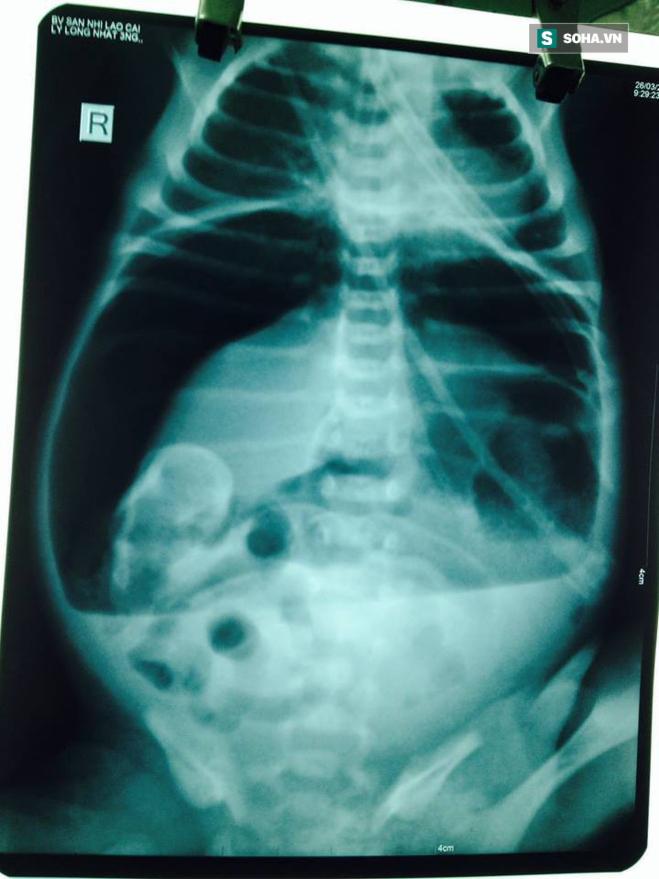

"Khi chúng tôi tiếp nhận trẻ ở trong tình trạng li bì, khó thở, tím, không sốt, bụng chướng căng, đặt sonde dạ dày có ít dịch màu xanh, bơm rửa trực tràng dịch nhày nâu lượng ít. Ngay sau đó trẻ được hồi sức tích cực bằng cách: trợ hô hấp, nuôi dưỡng hoàn toàn bằng đường tĩnh mạch, X-quang ổ bụng có hình ảnh mức nước - hơi và liềm hơi dưới cơ hoành.

Với tình trạng trẻ như vậy, chúng tôi đã hội chẩn cùng Ths.BS Đinh Ngọc Dũng - Trưởng khoa Ngoại tổng hợp - Bệnh viện Đa khoa tỉnh Lào Cai và chẩn đoán: Viêm phúc mạc do tắc ruột phân su biến chứng vỡ tạng rỗng", bà Nguyệt thông tin. Khi tiến hành phẫu thuật cấp cứu cho cháu bé, kíp phẫu thuật bất ngờ phát hiện dạ dày trẻ có cấu trúc bất thường. "Toàn bộ mặt trước không có lớp cơ chỉ có niêm mạc và thanh mạc, một đường vỡ lớn từ tâm vị đến hang vị. Các bác sỹ đã tiến hành cắt lọc và khâu phục hồi dạ dày", bà Nguyệt cho hay.